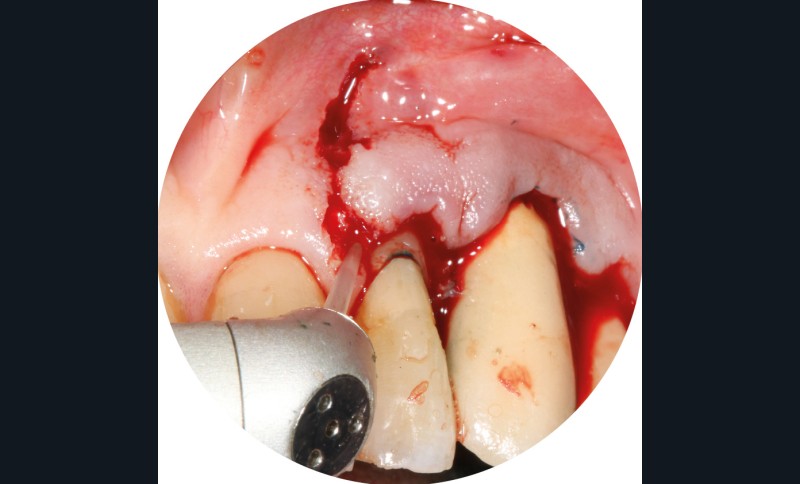

– Le laser Er-YAG, utilisé pour le nettoyage, est un laser avec un milieu actif composé d’yttrium, d’aluminium et de grenat dopé à l’erbium. Avec une longueur d’onde de 2 940 nm situé dans l’infrarouge, le laser Er-YAG est un laser à haute énergie, dont la lumière est absorbée dans l’eau et dans l’hydroxyapatite et qui ne pénètre pas profondément. Ceci permet de couper des tissus mous et des tissus durs, mais également de désorganiser le biofilm bactérie.

C’est un laser idéal pour le traitement chirurgical des péri-implantites. Il permet l’élimination du tissu de granulation à la surface de l’implant et de l’os ainsi qu’une décontamination mécanique par effet photoablatif.– Le laser Diode, utilisé pour la décontamination…